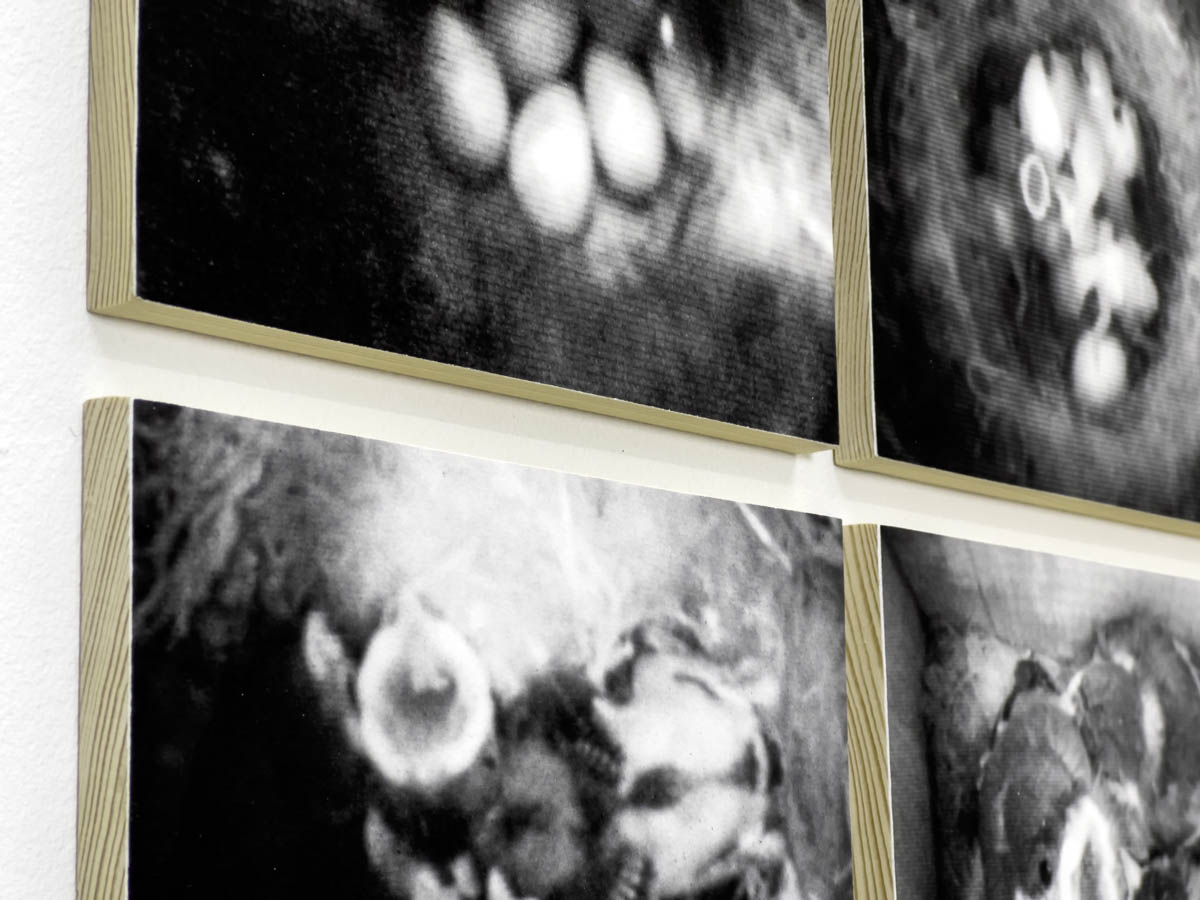

Découpe et gravure laser sur plexiglas, acier chromé 94 x 82 x 228 cm

41 coupes ont été sélectionnées et dessinées pour reformer le corps de Joseph Paul Jernigan, exécuté par injection au Texas en 1993. Ayant légué son corps à la science, il a été sectionné en 1878 tranches de 1 mm puis entièrement numérisé, ce qui a permis la création en 1994 du Visible Human Project, premier corps humain virtuel.